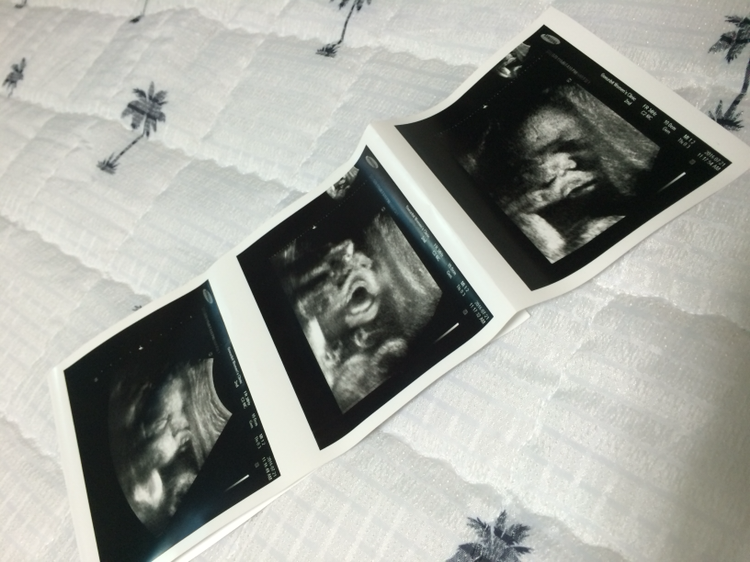

초음파 검사를 통해 아이를 보니 아이는 3주 동안 400g이 늘어 체중이 고작 2.4킬로란다. 선생님께선 또 아이가 주수보다 작다고 하셨다. 저번 검사 땐 3주 동안 800g이 늘었었는데 이번엔 고작 400g만 늘었다니. 영양분이 없어서 그런가... 난 또 자책하게 되었다. 그것도 그럴 것이 오늘 초음파를 통해 본 아이의 모습은 뭔가를 자꾸 먹고 싶은지 입을 오물오물하고 있었기때문이다. 그 모습에 마음이 더 아팠다. 무거운 마음을 안고 집으로 돌아가던 길. 여기저기 인터넷을 찾아보니 막달에 태아가 작으면 태아를 키우기 위해 수박을 많이 먹는다고 적혀 있었다. 이제 마지막을 위해 더 관리해야할 것 같다. 이젠 병원도 일주일에 한 번씩 검진을 가야 한다. 다음 주 검진 때는 아이가 조금 더 많이 커있었으면 좋겠다.